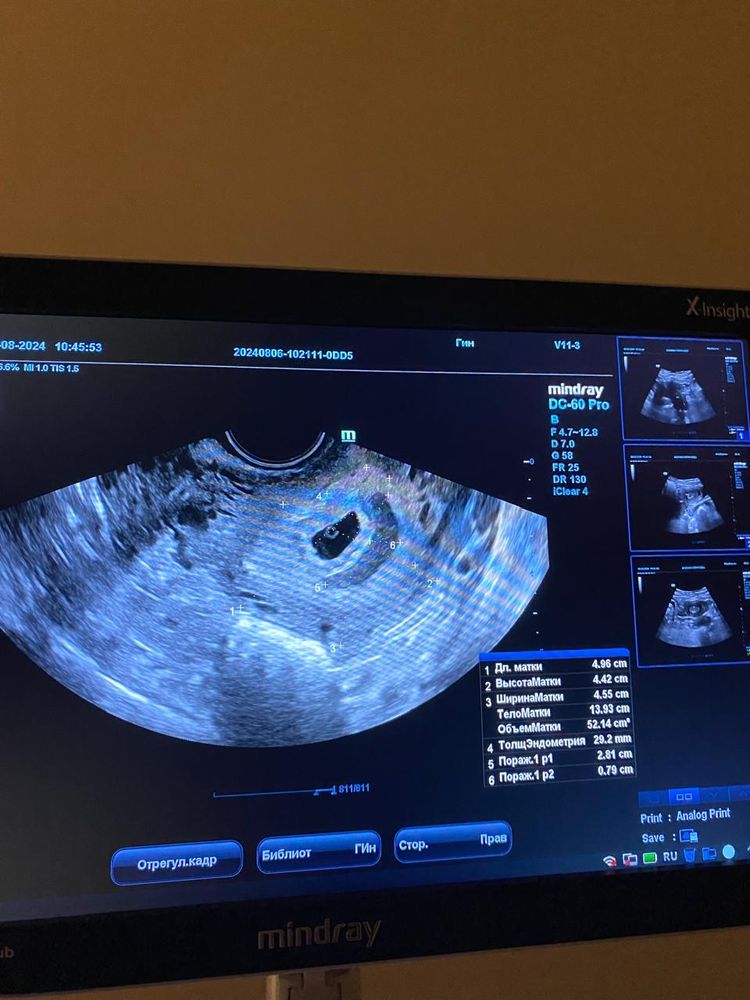

УЗИВ пятницу была на узи , все хорошо, вчера пошла на узи , нашли гематому , сегодня опять пошла что б убедиться , её подтвердили

выделений нет , живот не болит , гематома 3см почти